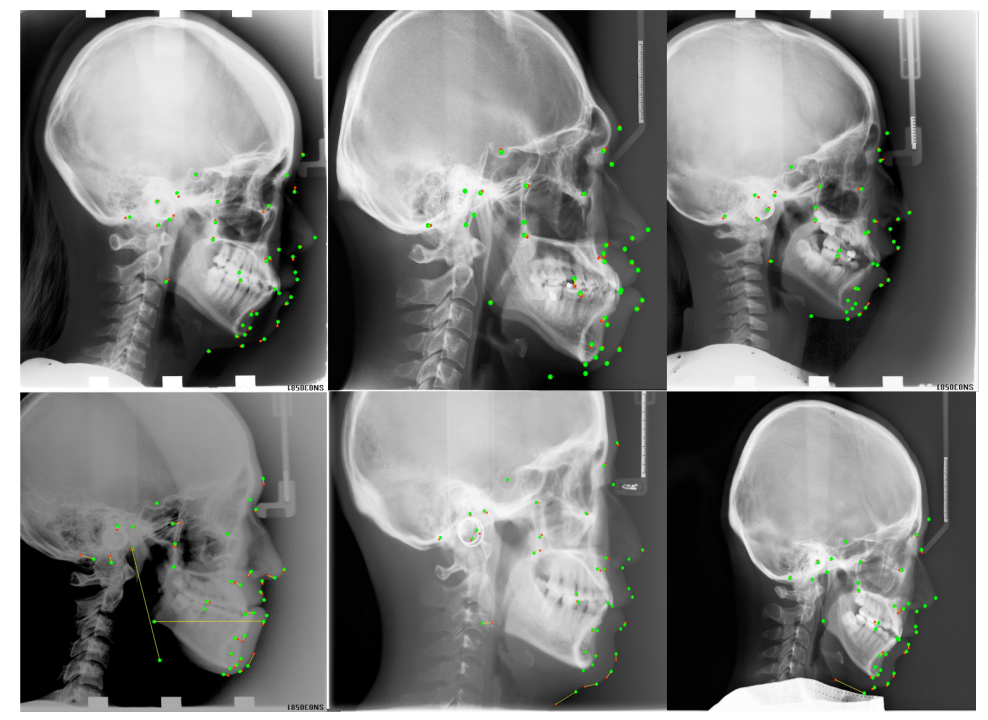

可视化的结果展示

图中,红色是预测点,绿色是金标准,黄色的线为对应金标准和预测点两个点连接的直线,长短可视化表示了误差大小。